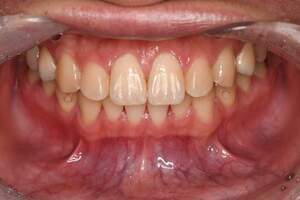

歯石除去

治療前

治療後

| 年齢 | 36歳・男性 |

|---|---|

| 主訴 | 歯石をとりたい |

| 治療内容 | 歯石除去 |

| 治療期間 | 30分 |

| 費用 | 約2,000円 |

| リスク・副作用 | ・歯ぐきの炎症が強いと歯石を取る際に出血することがあります。 ・処置後に歯がしみることがあります。 ・歯と歯の間に隙間ができるので、息が漏れ発音しにくいと感じることがあります。 ・歯ぐきの炎症が軽減すると歯ぐきが引き締まり、歯が長く見えることがあります。 |